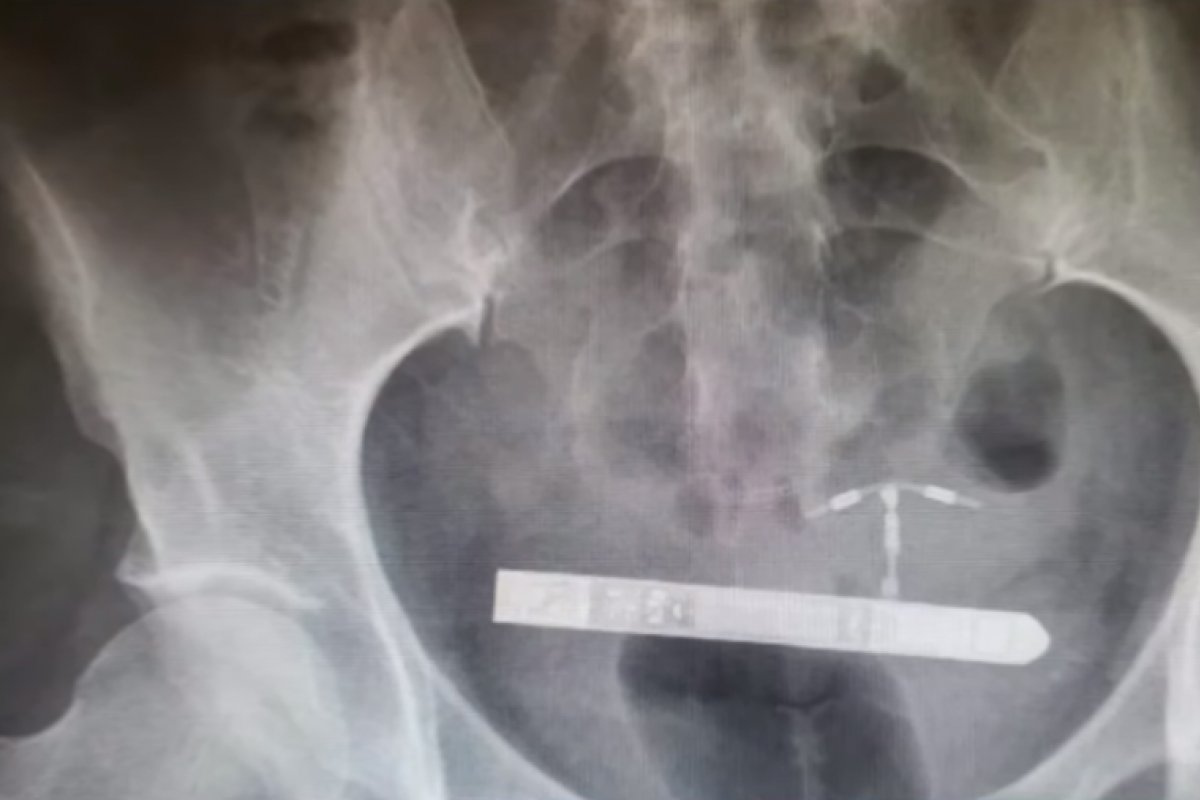

Uma norte-americana teve que realizar um procedimento cirúrgico após um vibrador ficar "emperrado" na bexiga dela durante uma "brincadeira sexual" com o namorado.

De acordo com o site Women's Healt, o objeto possuía cerca de 9 centímetros e teria entrado na bexiga da mulher enquanto ela jantava com o namorado. Após o ocorrido, ela foi encaminhada para um hospital, onde foi encaminhada para uma sala de cirurgia para a realização de exames e raio-x.

Segundo os médicos, o objeto teria entrado pela uretra da mulher e se alojado ao lado da bexiga. Depois de identificar a localização do objeto, a equipe médica realizou a cirurgia e removeu o vibrador.

O objeto, de cerca de 9 centímetros, teria entrado pela uretra da mulher e se alojado ao lado da bexiga. | Foto: Reprodução